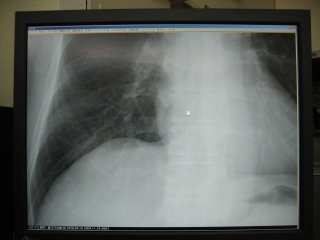

縮小率100%でアナログX線画像と同じサイズであり、モニター画面であるが、アナ

ログX線フィルム画像よりも美しく鮮明である。

写真4.制御装置のモニターにX線画像が表示

写真5.LF−C1のモニターに等倍表示

写真7.等倍表示、 写真8.拡大表示

写真9.従来のフィルムに近い表示 写真10.処理を強調した表示

写真11.濃度を下げた表示 写真12.濃度を上げた表示

写真13.ロー・コントラスト 写真14.ハイ・コントラスト

写真15.腫瘍検出用表示 写真16.反転表示

6)モニター表示ができる

X線撮影後、約2分で診察室に置いたモニターに撮影したX線画像が表示されます。これを等倍表示にしておくと、モニターには通常のアナログX線フィルムと同じ大きさで表示されます。EIZO 21.3インチの液晶モニターに表示された画像は、アナログX線フィルよりも鮮明で、これだけ鮮明なら臨床的にはフィルムに勝るとも劣らないと思います。その画像が従来のフィルム現像よりもかなり早く表示されるのだから非常に有用です。(写真5参照)